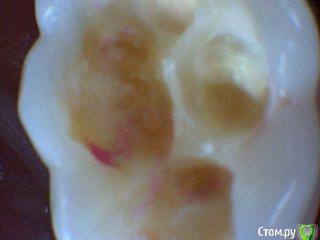

Давлетшин Опубликовано 15 мая, 2017 Поделиться Опубликовано 15 мая, 2017 (изменено) Есть такое слово НАДО. И надо делать ОПТГ в 6-7 лет. Здесь должна быть работа с рентгенологом. Можно отправлять снова и снова на снимки., пока не научится делать, с первого раза. Пусть рентгенолог объяснит позицию " чтобы не облучать". только цифрами и норм. актами. ну а потом и расстрелять можно, только не вы расстреливайте, а родители, за работу спрос с ВАС, а как вы можете сделать качественную диагностику и лечение без снимков. Вообще мне кажется на форуме, надо как то писать, когда задается вопрос, кто в каких условиях работает. может и более правильные рекомендации давали бы. Я дам одну рекомендацию. После 6-7 лет всех на ОПТГ. хоть за 100 км. через 15-20 ОПТГ пойдут"неожиданности" и еще больше укрепитесь в нужности исследования. На десерт неожиданность. Причем подозрение как то интуитивно вышло. Коментировать фото "какой я хороший/плохой, почему без кофера?" не буду. Скажу что был индикатор. И по вашему профилю ВЫ из Молдовы. интересно на одном ли языке мы говорим? Я про молочные премоляры. Мы в России то по разному думаем хотя программа в институтах одинаковая. Изменено 15 мая, 2017 пользователем Давлетшин 1 Ссылка на комментарий